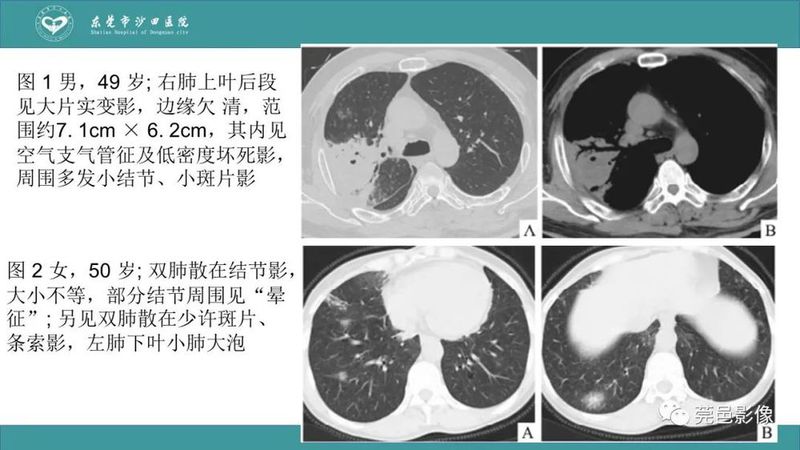

「肺炎克雷伯杆菌肺炎」影像学诊断+鉴别诊断